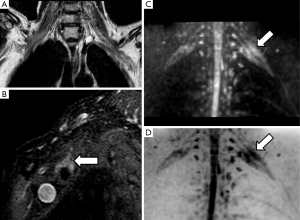

PN are highly anisotropic structures with a marked diffusion restriction in its perpendicular plane and facilitated diffusion along its main axis (7). These physiological features allow to use DWI for the study of PN, lumbar or brachial plexus. DW-based neurography (DWN) benefits from the use of gradients with the maximum strength to maintain the high signal of PN, while reducing the signal of surrounding tissues (8). PN and plexus can be highlighted from the rest of adjacent structures by applying one or two motion probe gradients perpendicular to the course of the nerve (Figure 1). In DWN, a high b value between 500 to 1,000 s/mm2, usually b 800 s/mm2, is acquired providing a good signal to noise ratio (SNR) and adequate suppression of neighboring structures (9). The inclusion of a fat-suppression technique in DWN sequences is mandatory, which may be performed using spectral or non-spectral fat suppression techniques. Diffusion weighted imaging with background signal suppression (DWIBS), a sequence designed particularly for whole-body applications, benefits from the use of short-tau inversion recovery (STIR), a non-selective, non-spectral fat suppression technique to increase the contrast of nerve structures with background structures, allowing at the same time to studying wider fields of view than DWN sequences based on spectral fat suppression techniques such as spectral presaturation with inversion recovery (SPIR) or spectral attenuated inversion recovery (SPAIR), which can be used for specific evaluation of determined anatomical regions (10).

DWN allows an accurate anatomical representation of PN by means of a fast and easy post process. Using an algorithm with maximum intensity projection (MIP) reconstruction of the obtained dataset, the PN are nicely shown, employing either conventional grey scale, or in the case of brachial or lumbar plexus inverted grey scale can be used for a better display.

Radiation induced brachial plexus damage in oncological patients is another not uncommon clinical scenario (51). In spite of new modulated radiation therapy techniques for head and neck or breast cancer treatment, post-radiotherapy brachial plexus neuropathy has to be considered when oncological patients with suspicion of brachial plexus involvement are evaluated (Figure 8). DWN shows nerve root thickening with increased signal intensity on high b values and also increase of ADC. Moreover, in these patients, DWI has the added value to rule out malignant infiltration of brachial plexus which typically shows lower ADC values with or without associated soft tissue abnormalities. Besides, DTI through 3D neurographic reconstructions is able to demonstrate infiltration, disruption or displacement of the involved nerve roots (43).

Brachial plexus roots and trunks on DTI after a direct or an indirect trauma demonstrate similar variations of FA or RD values to those described above for PN injuries. Neuropraxia of brachial plexus roots will show a decrease of FA values, due to loss of fiber organization, and increase of RD values (Figure 9). The amount of these changes is directly related to the severity of the neural damage and may be consider as a complementary tool to the clinical and electrophysiological evaluation (52).